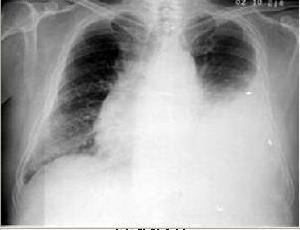

1、X 線胸片 少量積液可僅表現為患側肋膈角模糊、變鈍或消失;中等量積液可見患側下胸部大片均勻的緻密陰影,上緣呈外高內低的弧形;大量積液時患側胸部呈大片均勻的緻密陰影,氣管和縱隔對側移位,患側膈肌下移;包裹性積液表現為大小不等的圓形或半圓形均勻的緻密陰影,邊緣光滑清晰;葉間積液在側位片上呈長軸與葉間裂一致的邊緣銳利的梭狀均勻的緻密陰影;肺底積液在正位片上易與膈肌升高混淆,患側臥位透視或拍片則可見膈肌水平正常,胸水沿下側胸壁分布。X 線檢查不僅可以診斷積液,而且有助於原發病的診斷。

3、惡性胸腔積液 原發癌以肺癌和乳癌為主,其次為淋巴瘤,少數為卵巢癌、胃癌、子宮腫瘤等。腫瘤引起胸腔積液的直接機理有胸膜轉移,使血管通透性增加;胸膜淋巴引流受阻,縱隔淋巴結阻塞淋巴回流;胸導管受阻;支氣管阻塞使胸膜腔壓力減低;心包受累(血管靜水壓升高,產生漏出液)。間接機理有低蛋白血症;阻塞性肺炎;肺栓塞以及放射治療併發症。惡性胸腔積液除有腫瘤本身許多症狀外,臨床上常有氣促、消瘦、胸痛、乏力及納差。X 線檢查可見從小量至全胸積液,積液量大時,肺內和縱隔淋巴結腫瘤陰影常不易辨認,此時CT 檢查能顯示病灶。惡性胸液常為血性,抽液後迅速生長,胸液檢查包括常規、細胞學、酶譜、癌胚抗原等,胸液中找到癌細胞為惡性胸腔積液確診依據。由於癌腫多先位於髒層胸膜,而壁層胸膜上可能僅散在分布,故胸膜活檢時陽性率不高。